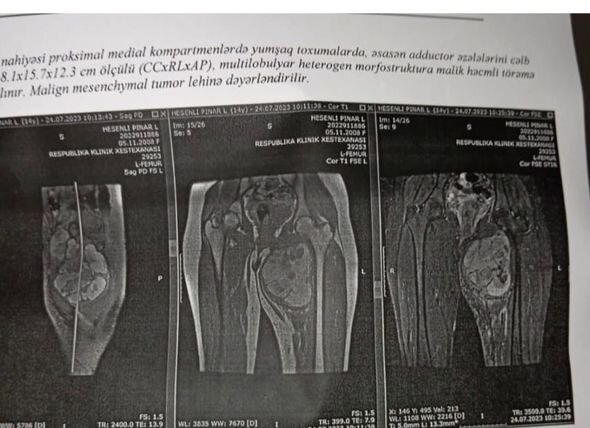

"Hər şey Pınarın idman dərsi zamanı yıxılaraq ayağını zədələməsi ilə başladı. Həkim bizi əmin etdi ki, heç nə yoxdur. Biz yay tətilinə qədər gözlədik və sonra qızımızı Bakıya apardıq. Onlar maqnit rezonans tomoqrafiyası etdilər, ardınca biopsiyanı təhlil etdilər. Nəticədə qorxulu diaqnoz qoyuldu - sarkoma".

Bu barədə Abşeron rayon, Saray kənd sakini, yeganə qızı xərçəng xəstəliyindən əziyyət çəkən Ramila Həsənova Media.Az-ın redaksiyasına müraciətində danışıb.

Onun sözlərinə görə, gec müraciət etdikləri və metastaz başladığı üçün həkimlər məyusedici proqnozlar veriblər.

"Beləliklə, Pınarı Türkiyəyə gətirdik, orada müalicə etməyə hazırdırlar. Metastazlar qaraciyərə təsir etdi, buna görə də orada maye yığılır. Qızıma mayenin boşaldılması üçün xüsusi boru qoyulmuşdu... Bu səbəbdən ayaqları çox şişdi. Pınar da kimyaterapiya alır və proses çox ağır keçir", - deyə o vurğulayıb.

15 yaşlı Pınar hazırda ikinci aydır ki, Ankarada xəstəxanada müalicə olunur. Ailənin artıq pulu qurtarıb, qarşıda 15 min manatlıq əməliyyat gözlənilir.

"Növbəti mərhələ əməliyyatdır, amma bizim bunun üçün heç bir vəsaitimiz qalmayıb. Bundan əvvəl qohumlarımız bizə kömək edirdisə, indi onların maddi imkanları tükənib. Nə edəcəyimizi belə bilmirik. Pula qənaət etmək üçün Ankarada kirayədə deyil, qızımla xəstəxana otağında qalıram. Yoldaşım taksi sürücüsü işləyir, ayda 350-400 manat maaş alır. 15 min manat toplamaq lazımdır. Bunun 12 mini əməliyyat, 3 mini isə dərman xərcləridir. Xahiş edirəm yeganə qızımı xilas etməyə kömək olun. Yaxşı oxuyurdu, müəllim olmaq istəyirdi..." - deyə Pınarın anası kömək istəyir.